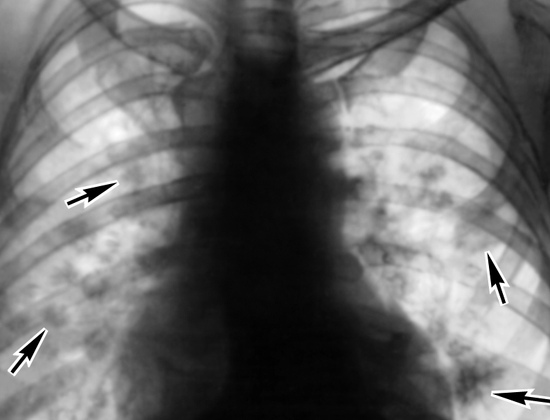

Снижен аппетит. Иногда субфебрилитет. Могут быть головные боли. Общая слабость. При большом количестве личинок возможно образование в легких летучих инфильтратов.

image

В крови эозинофилия. Чаще всего эти проявления болезни расцениваются как ОРЗ.